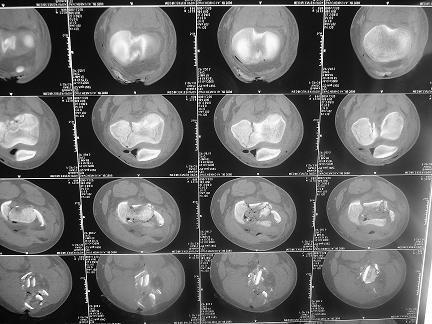

Тяжелый открытый внутрисуставной перелом дистальной части бедренной кости и открытый голени в средней трети,множественные раны и некрозы на голени. Что делать?

4 суток после мотоциклетной травмы. 16 лет. Переведен из районной больницы, где основные раны на голени и бедре были ушиты наглухо и наложено скелетное вытяжение за бугристость и пятку, через 2 суток. При поступлении - высокая лихорадка, анемия. Из сопутствующих только сотряс. Раны на бедре и голени расскрыты, обработаны. На передней поверхности бедра рана с начавшимся нагноением, около 15х8см, полость распространяется от места перелома, где значительная часть отломков практически лишена связи с мягкими тканями, до верхней трети, откуда удалена гематома 200мл. 4-главая мышца повреждена, отрыв и перелом без смещения надколенника. Проксимальный отломок бедренной кости на протяжении 20см на 2 трети окружности лишен надкостницы. Резко выраженный отек бедра. На голени рана на передней поверхности 12 х 5см, дном является лишенная надкостницы большеберцовая кость, некроз краев раны. Множественные раны и участки некрозов кожи в области коленного сустава, обширные некрозы на голени в нижней и верхней третях. Пульсация на стопе отчетливая, при этом некрозы в нижней трети голени постепенно увеличиваются. Сейчас на ИВЛ с клиникой респираторного дистресс синдрома. Что делать - неясно. Возможен ли при таком переломе бедра интрамедуллярный остеосинтез? Было бы здорово фиксировать оба перелома через 1 доступ.